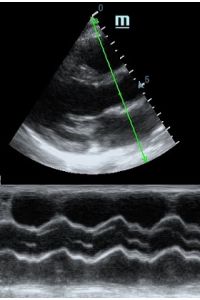

MAPSE - амплитуда движения латерального кольца митрального клапана, позволяет рассчитать фракцию выброса по формуле EF = 4.8 × MAPSE (mm) + 5.8, очень быстрый и гораздо более точный («прародитель Strain») метод чем широко распространенный метод Teicholtz. В современных приборах можно легко добавить свою формулу при отсутствии ее в стандартном калькуляторе. Главным условием является проведение линии М-режима параллельно стенке левого желудочка в апикальном четырехкамерном сечении, что легко достигается при использовании функции Free Xros.